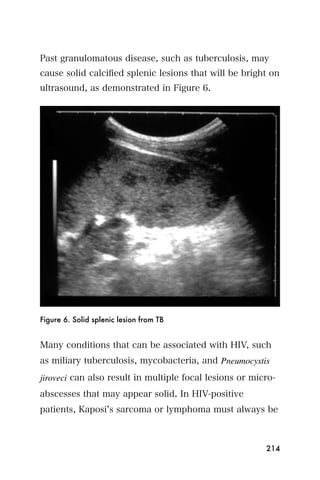

longitudinal axis, rotate the transducer 90 degrees

counterclockwise, so that the index marker is pointing

toward the patient s back, as in Figure 12. In this

position, a transverse view of the kidney will be seen.

Repeat the process of fanning as in step 2, but this